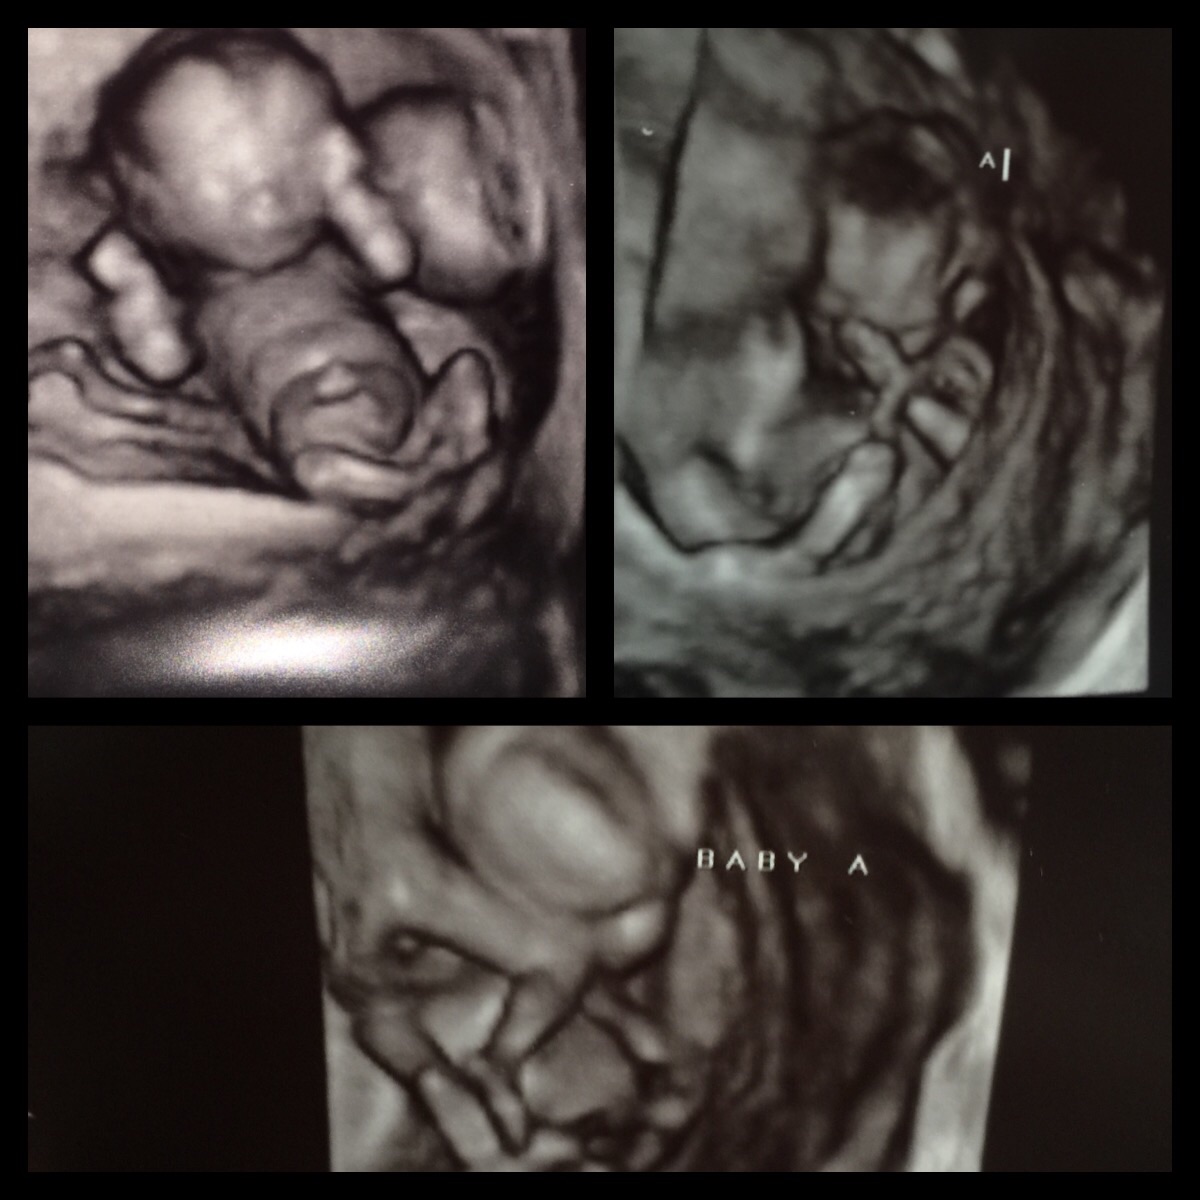

We booked our 3D/4D ultra sound @ 15 weeks they give you a 2D for gender reveal because it is so early and a sneak peek 3D/4D. Found out we are having a BOY! Which we both selfishly wanted ☺️ the package also gives you a teddy bear with a recording of baby's heart beat! I've been carrying around this bear as if I was a 5 year old little girl! Too excited!